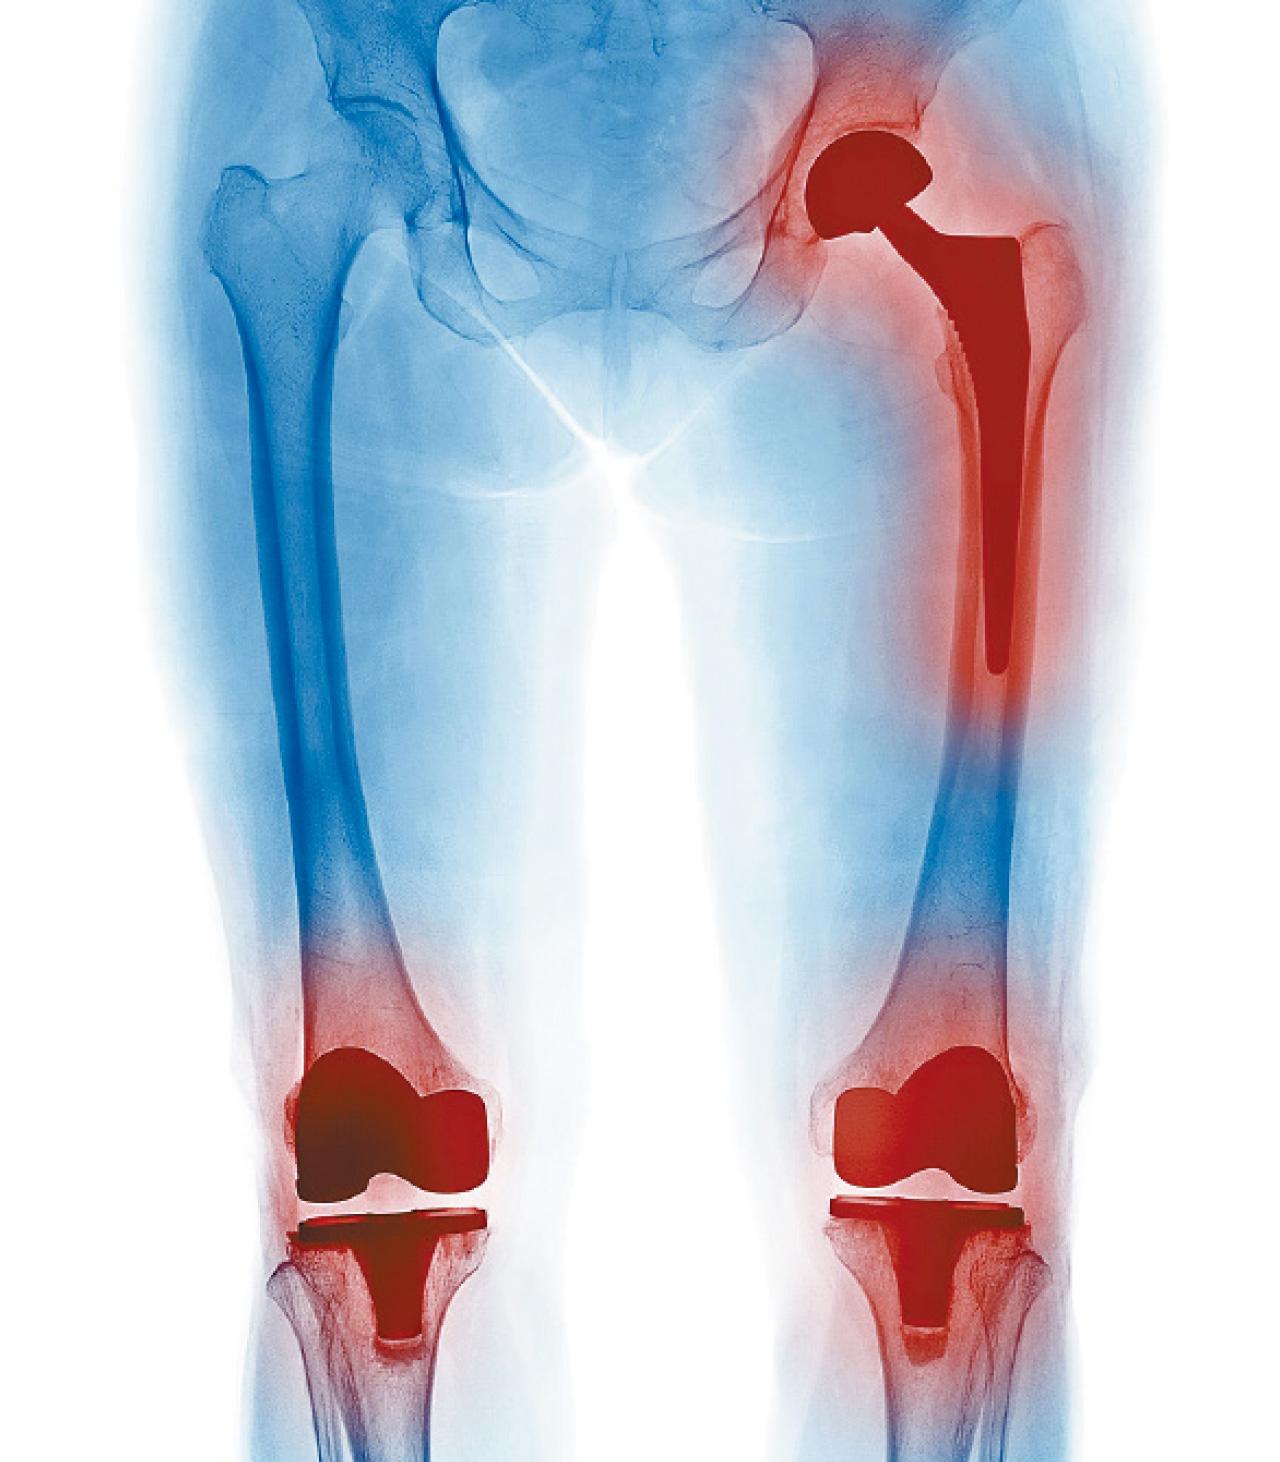

骨組織感染主要由細菌引起,而細菌可趁人體免疫力下降乘虛而入。常見的骨組織感染包括糖尿病腳、術後感染和創面感染:前者由於血管和神經線受糖尿病影響,令傷口易受細菌感染;後者有可能發生於需要植入金屬支架(如置換關節)的病人,即使手術室已採取嚴格的無菌措施,手術後亦有可能出現骨組織感染,或有細菌於金屬植入物表面上繁殖。患者一旦受細菌感染,會發燒、白血球持續過高,或惡化至可危及性命的敗血症。

在港大醫學院臨床醫學學院矯形及創傷外科學系,我們會把細菌樣本送往病理科實驗室化驗以分辨細菌種類;讓微生物學專家從而針對性提出使用合適的抗生素作為治療。如細菌於金屬表面形成細菌膜,能抵禦抗生素的攻擊,唯有使用較強力的抗生素方可有效殺死細菌,但傷口仍有可能再受感染。若抗生素未能發揮作用,醫生會為患者持續施行清創術,刮走植入物表面細菌膜和清洗傷口。當清創術未能控制細菌感染,醫生會把植入物拆除,並注射抗生素,待患者痊愈後再植入新的人工關節或支架,而患者及後需服用抗生素一段時間。這對患者來說可算是「長期作戰」;而過度使用抗生素可令細菌變種,產生耐藥性,治療上會更棘手。